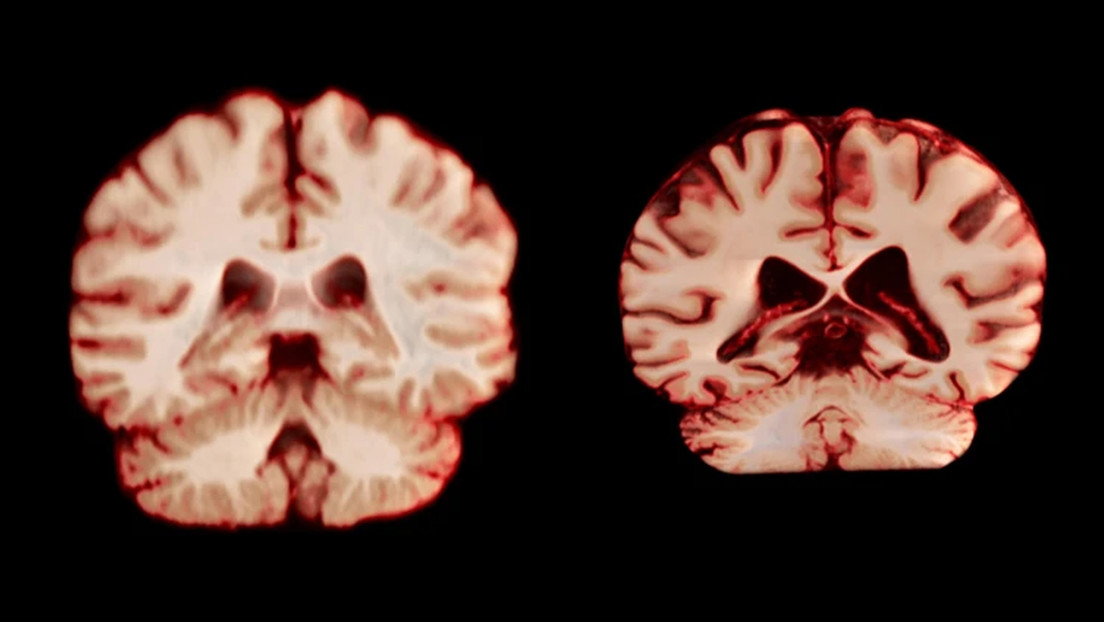

La ciencia confirma: el cerebro de los hombres envejece más rápido

Los sencillos hábitos que ayudarán a tu cerebro a mantenerse joven toda la vida